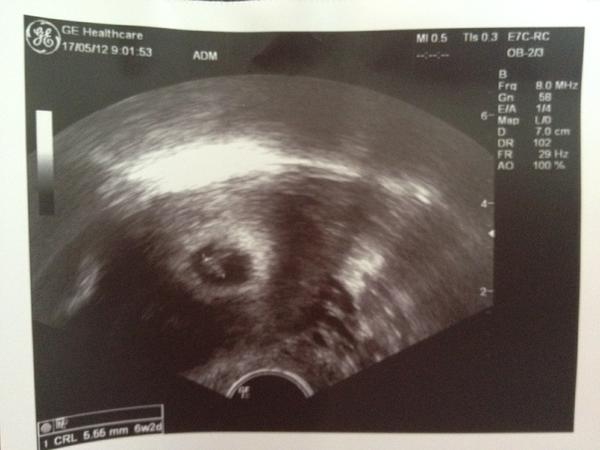

@mia75 (Obilní trh Brno) 2.IVF duben/12 (2 E), 17. 5. UZV 6+2tt – 1 mimi, blahoželáme ku srdiečku!!! 😵 😵 😵

@vall83 (CAR v Německu) 1.IVF březen/12 (2 E), UZV 15.5. – 5+2tt vypadá to na 1 mimi, další UZV 25.5.